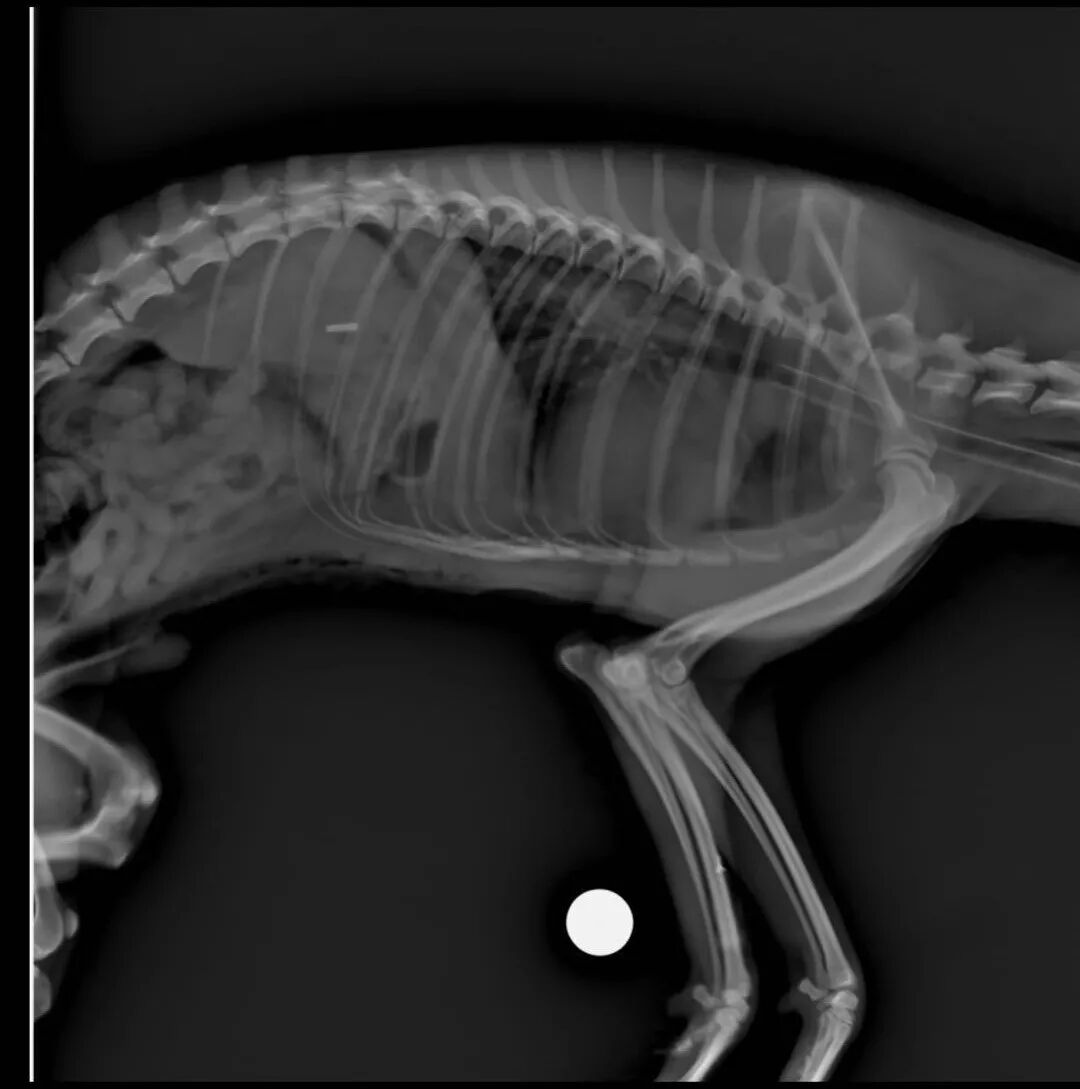

▲X光

▲X光平拍